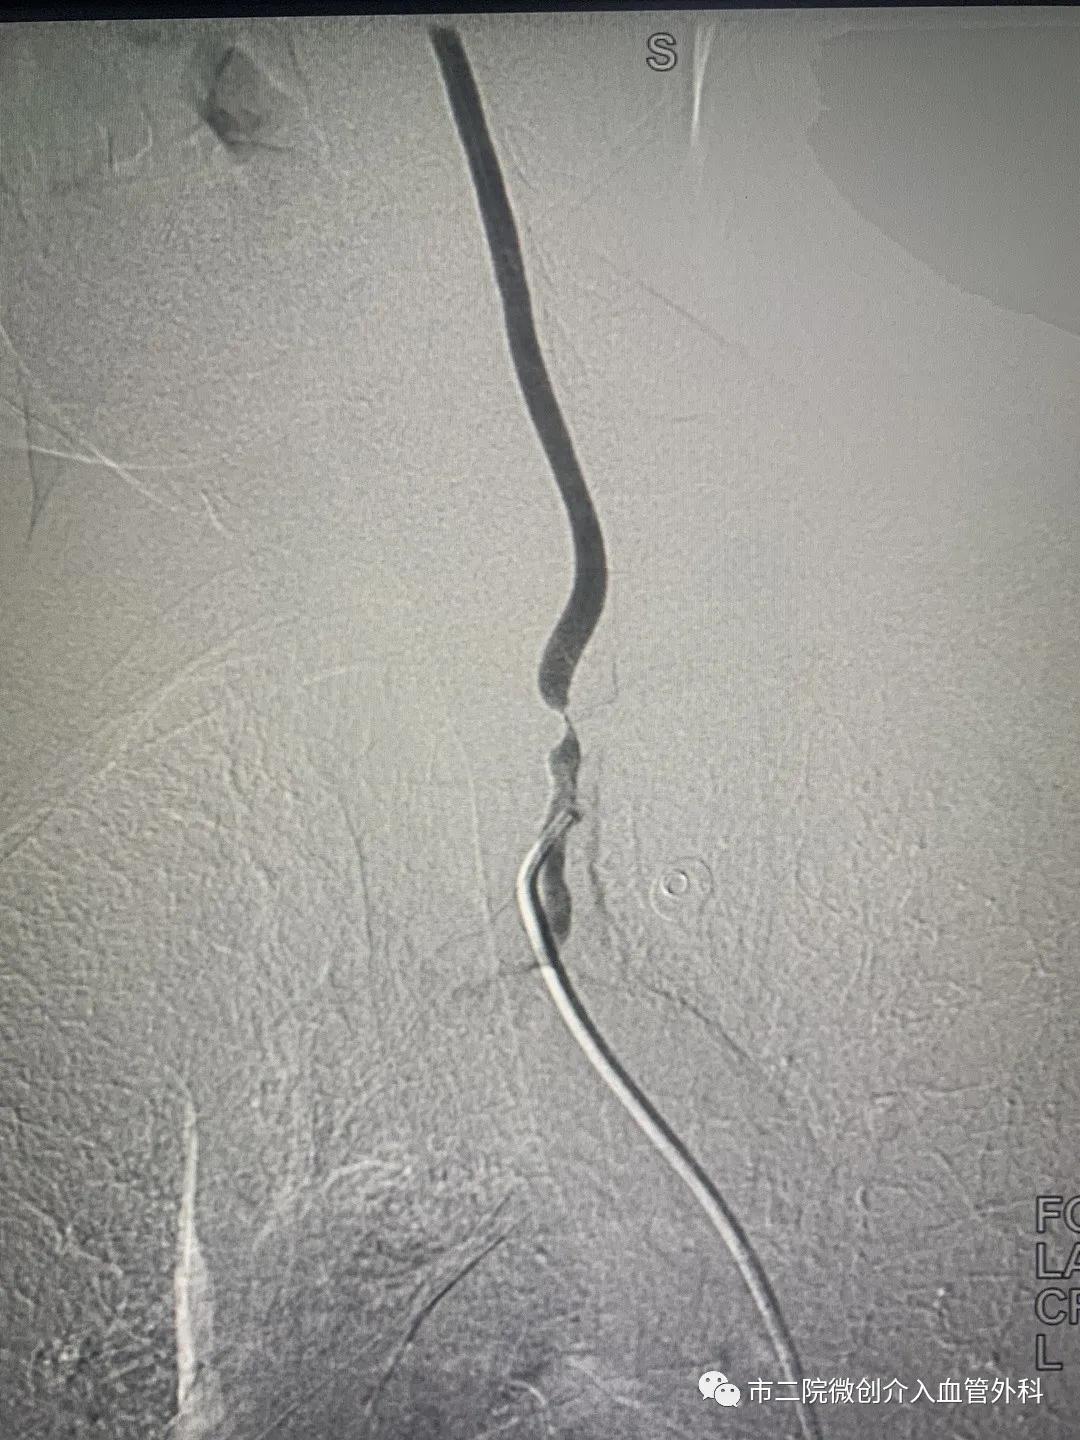

患者王某、男性、60岁以“发现左上肢脉搏、血压消失伴肢体麻木皮温减低”前来就诊。入院后完善相关检查,进行脑动脉造影,造影提示:左侧锁骨下动脉完全闭塞,左侧椎动脉重度狭窄。

术中造影

术中利用导丝缓慢通过狭窄的左侧椎动脉引入球囊进行扩张,紧接着精准释放支架,再次造影椎动脉狭窄段消失,血流通畅,闭塞的左侧锁骨下动脉也开始有血流经过。一举两得,既解决了左侧椎动脉重度狭窄的问题,闭塞的锁骨下动脉也随之开通,患者各项生命体征平稳,手术顺利结束。